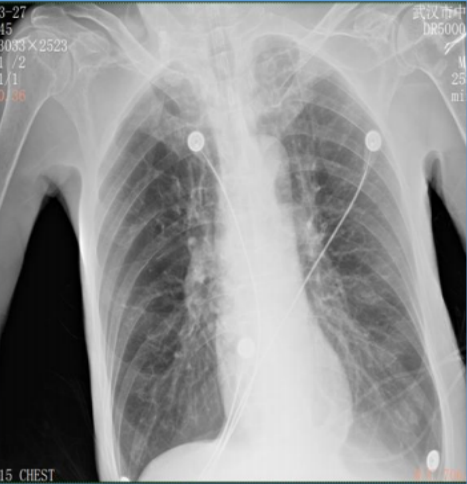

• 胸部X线检查双肺多发实性结节,慢性支气管炎;肺气肿,双下肺感染图1

图1  患者胸部X线检查